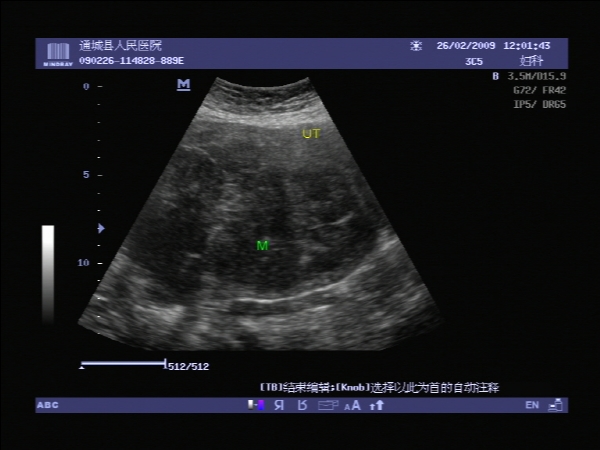

盆腔彩超报告:子宫肌瘤。(或许也漏诊了!)

是尿滁留还是占位----b超